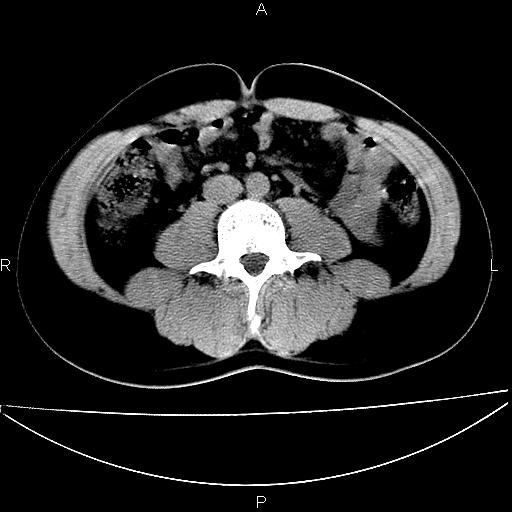

男 25岁 自述 尿频尿急,排尿困难20多天.无腰痛, b超说左肾盂轻度积水,左输尿管上端扩张.未见结石影. ct我看双侧肾盂轻度积水,双输尿管上端都扩张,大家看看能看见结石吗?

正常变异。

考虑肾外肾盂 前列腺轻度肿大 密度欠均 考虑炎性改变

箭头所指不是输尿管,壶腹型肾盂。

肾外肾盂,必要时+c